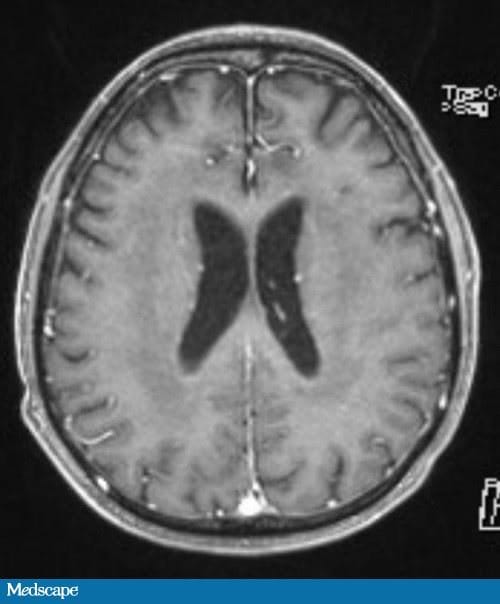

Neste caso, o paciente fez quimioterapia intratecal com metotrexato/citarabina/hidrocortisona três vezes por semana, seguida de ácido folínico durante três semanas quando seu líquido cefalorraquidiano estava com celularidade e citologia normais. Após a normalização do liquor, ele recebeu tratamento triplo intratecal semanal durante quatro semanas e a seguir a cada duas semanas, por um mês. Ele evoluiu com diarreia e desequilíbrio da marcha. Foi feita RM de crânio e da coluna vertebral, visto que o liquor estava normal (Figura 2).

A RM medular foi normal. A RM de crânio revelou alterações periventriculares na substância branca compatíveis com leucoencefalopatia. Ele também apresentava discreta fraqueza bilateral e reflexos tendinosos profundos reservados.